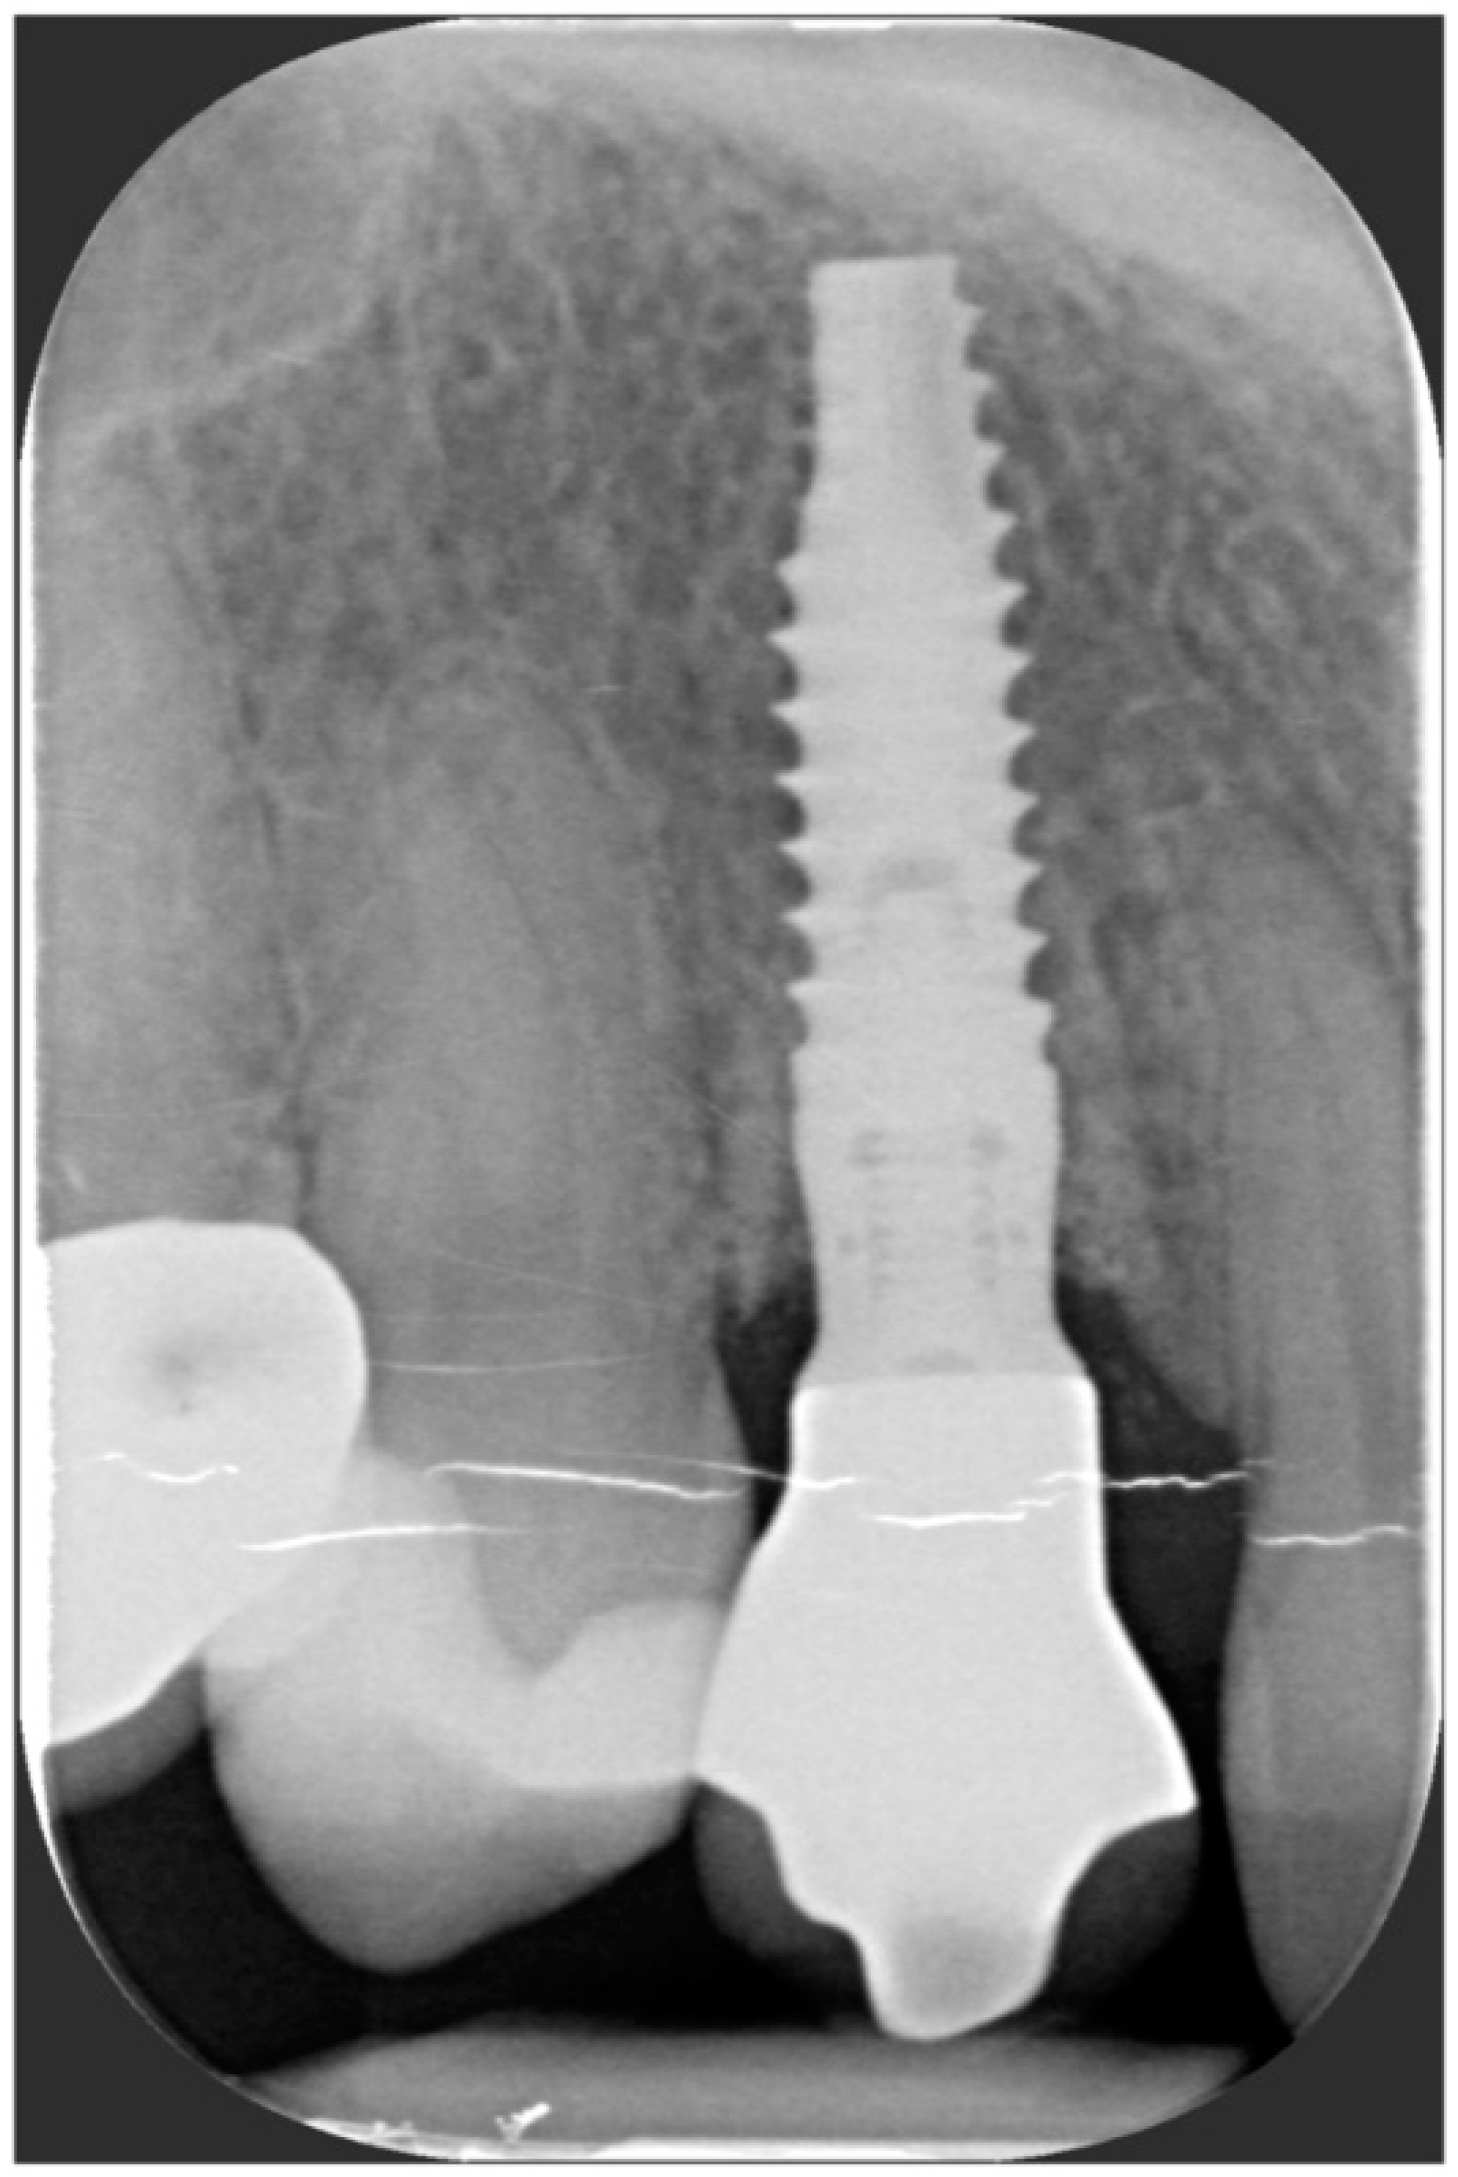

The implant site was prepared in a fully guided manner, using drills of progressively larger diameter, so that at the moment of guided implant insertion, the fixture could reach the pre-established position with enough primary stability to consent immediate provisionalization (35 Ncm) (Figure 6a,b). The implant shoulder should be palatal with respect to the imaginary line that connects the buccal profile of the adjacent teeth without placing it so that it is excessively palatal, in order to avoid creating prosthetic emergence profiles that are too horizontal, which are difficult to maintain in terms of hygiene.

After the complete closure of the papillae, a final sling suture suspended around the cingulum of the implant-supported crown (6/0 PGA thread; 11 mm needle) was performed to obtain a tight adaptation of the flap’s keratinized tissue into the convex, smooth surface of the provisional, a prerequisite for the stability of the surgical wound and for minimizing the risk of flap shrinkage. The absence of blood seeping from the margins is a sign of surgical wound stability, and this can minimize the contraction of the coronally advanced flap. At the end of surgery, an X-ray scan was performed (Figure 12).

Figure 12. Radiographic evaluation following implant placement.